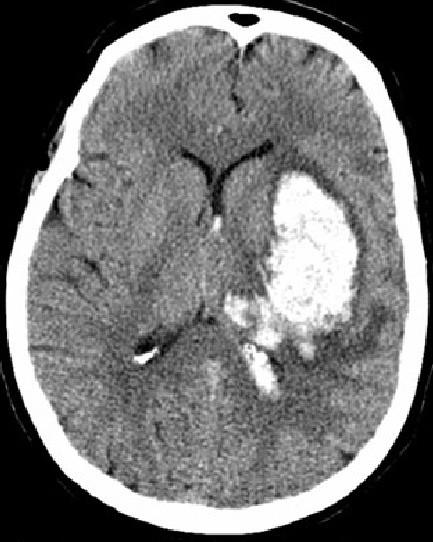

- Tomografia Computadorizada (TC)

De rápida execução, permite a diferenciação entre A.V.C. isquêmico e hemorrágico, monitoramento da evolução do A.V.C. e detecção de condições concomitantes.

AVC HEMORRÁGICO

(ÁREA BRANCA)